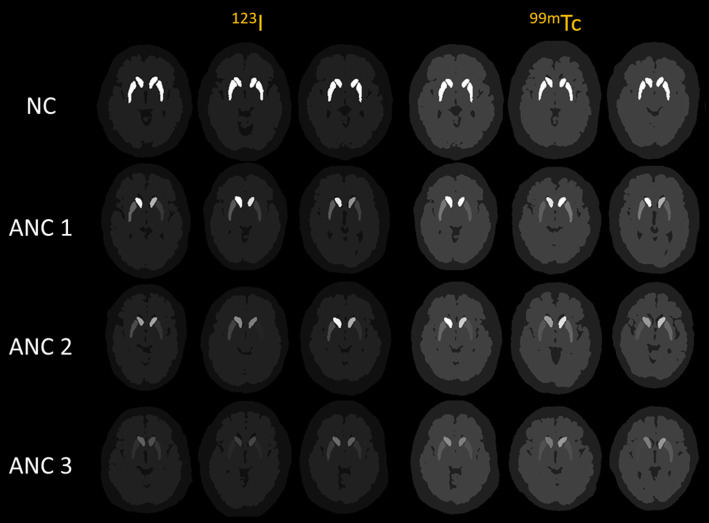

Results: A population of 1000 normal and abnormal PD phantoms was generated for both tracers. Visual comparisons and quantitative analyses demonstrated that simulated data exhibited high similarity to clinical data. Reconstructed images with AC + SC achieved the best quantitative results, followed by AC only, without AC and SC, and SC only.

{"title":"用于帕金森病放射性核素成像研究的数字脑影群的开发。","authors":"Wenbo Huang, Han Jiang, Guang-Uei Hung, Yonghua Zhao, Ruibing Wang, Greta S P Mok","doi":"10.1186/s40658-025-00787-8","DOIUrl":null,"url":null,"abstract":"<p><strong>Purpose: </strong>Dopamine transporter (DAT) SPECT is a powerful tool for early diagnosis of Parkinson's disease (PD), while digital phantoms and Monte Carlo (MC) simulations can serve as important research tools. This study aims to develop a novel digital brain phantom population for <sup>99m</sup>Tc-TRODAT-1 (<sup>99m</sup>Tc) and <sup>123</sup>I-ioflupane (<sup>123</sup>I) brain SPECT, and to assess attenuation correction (AC) and scatter correction (SC) in DAT SPECT.</p><p><strong>Methods: </strong>Striatum, brain background (gray and white matter), and cold regions (skull and cerebrospinal fluid) were segmented from 200 T1 MRI brain images from the PPMI dataset. Striatal binding ratio (SBR) values were retrospectively collected from 200 <sup>123</sup>I and 100 <sup>99m</sup>Tc DAT SPECT patients with suspected PD symptoms from PPMI and a local hospital, respectively. Various activity values were assigned to the randomly paired segmented regions according to a range of SBR values based on the SPECT Visual Interpretation (VI) assessment scheme. The new phantom population was combined with MC simulation tool SIMIND to generate realistic noisy projections. Quantitative accuracy of reconstructed images with attenuation correction (AC) and scatter correction (SC) was assessed.</p><p><strong>Results: </strong>A population of 1000 normal and abnormal PD phantoms was generated for both tracers. Visual comparisons and quantitative analyses demonstrated that simulated data exhibited high similarity to clinical data. Reconstructed images with AC + SC achieved the best quantitative results, followed by AC only, without AC and SC, and SC only.</p><p><strong>Conclusion: </strong>The developed digital DAT SPECT phantom population can be served for a wide range of PD applications. Attenuation impacts image quality the most in DAT SPECT, while AC + SC is effective to enhance image quality and quantitative accuracy of DAT SPECT.</p>","PeriodicalId":11559,"journal":{"name":"EJNMMI Physics","volume":"12 1","pages":"74"},"PeriodicalIF":3.2000,"publicationDate":"2025-07-29","publicationTypes":"Journal Article","fieldsOfStudy":null,"isOpenAccess":false,"openAccessPdf":"https://www.ncbi.nlm.nih.gov/pmc/articles/PMC12307856/pdf/","citationCount":"0","resultStr":"{\"title\":\"Development of a population of digital brain phantoms for radionuclide imaging research in Parkinson's disease.\",\"authors\":\"Wenbo Huang, Han Jiang, Guang-Uei Hung, Yonghua Zhao, Ruibing Wang, Greta S P Mok\",\"doi\":\"10.1186/s40658-025-00787-8\",\"DOIUrl\":null,\"url\":null,\"abstract\":\"<p><strong>Purpose: </strong>Dopamine transporter (DAT) SPECT is a powerful tool for early diagnosis of Parkinson's disease (PD), while digital phantoms and Monte Carlo (MC) simulations can serve as important research tools. This study aims to develop a novel digital brain phantom population for <sup>99m</sup>Tc-TRODAT-1 (<sup>99m</sup>Tc) and <sup>123</sup>I-ioflupane (<sup>123</sup>I) brain SPECT, and to assess attenuation correction (AC) and scatter correction (SC) in DAT SPECT.</p><p><strong>Methods: </strong>Striatum, brain background (gray and white matter), and cold regions (skull and cerebrospinal fluid) were segmented from 200 T1 MRI brain images from the PPMI dataset. Striatal binding ratio (SBR) values were retrospectively collected from 200 <sup>123</sup>I and 100 <sup>99m</sup>Tc DAT SPECT patients with suspected PD symptoms from PPMI and a local hospital, respectively. Various activity values were assigned to the randomly paired segmented regions according to a range of SBR values based on the SPECT Visual Interpretation (VI) assessment scheme. The new phantom population was combined with MC simulation tool SIMIND to generate realistic noisy projections. Quantitative accuracy of reconstructed images with attenuation correction (AC) and scatter correction (SC) was assessed.</p><p><strong>Results: </strong>A population of 1000 normal and abnormal PD phantoms was generated for both tracers. Visual comparisons and quantitative analyses demonstrated that simulated data exhibited high similarity to clinical data. Reconstructed images with AC + SC achieved the best quantitative results, followed by AC only, without AC and SC, and SC only.</p><p><strong>Conclusion: </strong>The developed digital DAT SPECT phantom population can be served for a wide range of PD applications. Attenuation impacts image quality the most in DAT SPECT, while AC + SC is effective to enhance image quality and quantitative accuracy of DAT SPECT.</p>\",\"PeriodicalId\":11559,\"journal\":{\"name\":\"EJNMMI Physics\",\"volume\":\"12 1\",\"pages\":\"74\"},\"PeriodicalIF\":3.2000,\"publicationDate\":\"2025-07-29\",\"publicationTypes\":\"Journal Article\",\"fieldsOfStudy\":null,\"isOpenAccess\":false,\"openAccessPdf\":\"https://www.ncbi.nlm.nih.gov/pmc/articles/PMC12307856/pdf/\",\"citationCount\":\"0\",\"resultStr\":null,\"platform\":\"Semanticscholar\",\"paperid\":null,\"PeriodicalName\":\"EJNMMI Physics\",\"FirstCategoryId\":\"3\",\"ListUrlMain\":\"https://doi.org/10.1186/s40658-025-00787-8\",\"RegionNum\":2,\"RegionCategory\":\"医学\",\"ArticlePicture\":[],\"TitleCN\":null,\"AbstractTextCN\":null,\"PMCID\":null,\"EPubDate\":\"\",\"PubModel\":\"\",\"JCR\":\"Q2\",\"JCRName\":\"RADIOLOGY, NUCLEAR MEDICINE & MEDICAL IMAGING\",\"Score\":null,\"Total\":0}","platform":"Semanticscholar","paperid":null,"PeriodicalName":"EJNMMI Physics","FirstCategoryId":"3","ListUrlMain":"https://doi.org/10.1186/s40658-025-00787-8","RegionNum":2,"RegionCategory":"医学","ArticlePicture":[],"TitleCN":null,"AbstractTextCN":null,"PMCID":null,"EPubDate":"","PubModel":"","JCR":"Q2","JCRName":"RADIOLOGY, NUCLEAR MEDICINE & MEDICAL IMAGING","Score":null,"Total":0}